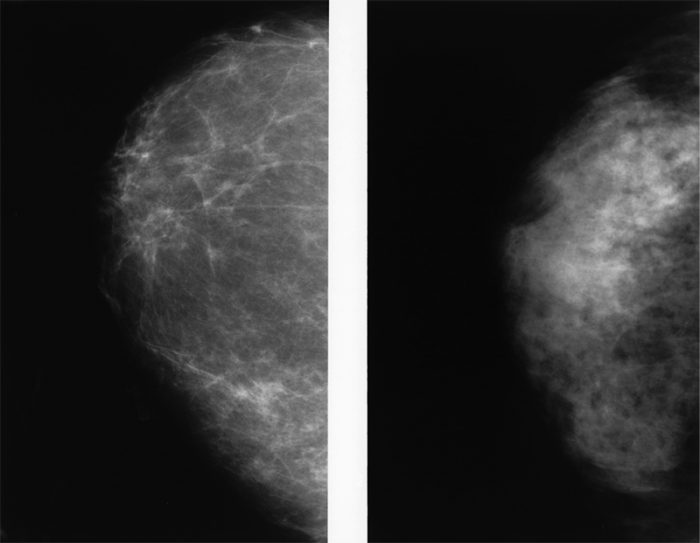

ではなぜ40歳代の女性においてこのような現象が起きるのだろう。代表的な理由の一つが、この年代でデンスブレストを高頻度に認めることである。デンスブレストとは、白色に描出される乳腺実質を広範囲に認めるマンモグラフィー画像を指す。デンスブレストの乳房においては、乳がんが存在していたとしても、背景乳腺に隠れてしまうため、乳がんの検出率が下がるのである。また、正常な乳腺組織を乳がんと誤って認識するようなケースも増加する。40歳代の実に半分以上がデンスブレストと判断される状態にある(4)。デンスブレストの頻度は年齢とともに減少するが、50歳代、60歳代の女性においても、40%以上、30%以上がデンスブレストと判断されており、50歳以上の女性においても無縁ではない。

▲写真 マンモグラフィーで写し出されるデンスブレスト(高濃度乳腺)(左)と脂肪の多い乳房(右)。出典:National Institutes of Health